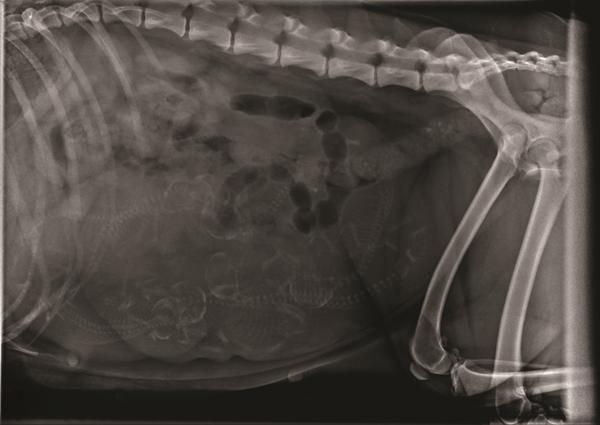

På trods at lidt tvivl om hvorvidt røntgen var go eller no-go, så endte jeg op med at tage imod det. Min dyrlæge anbefalede det, og det var hurtigt overstået.

Nu sidder jeg så med billederne fra røntgen, og studser over antallet af små vidundere. Jeg har siddet og leget lidt med kontrasterne, kigget efter kranier, rygrad, ribben.. Sammensat, gættet, kørt lidt frem og tilbage. Er kommet frem til mit umiddelbare gæt - men hvad er jeres?

Mht antallet, så var dyrlægens gæt 6, måske 7. Præcis som Malene har vist, med de to øverst til venstre, hvor deres kranier overlapper hinanden. Det var lidt lettere at se efter jeg fik rodet med kontrasten herhjemme, end på det lysere billede fra dyrlægen.